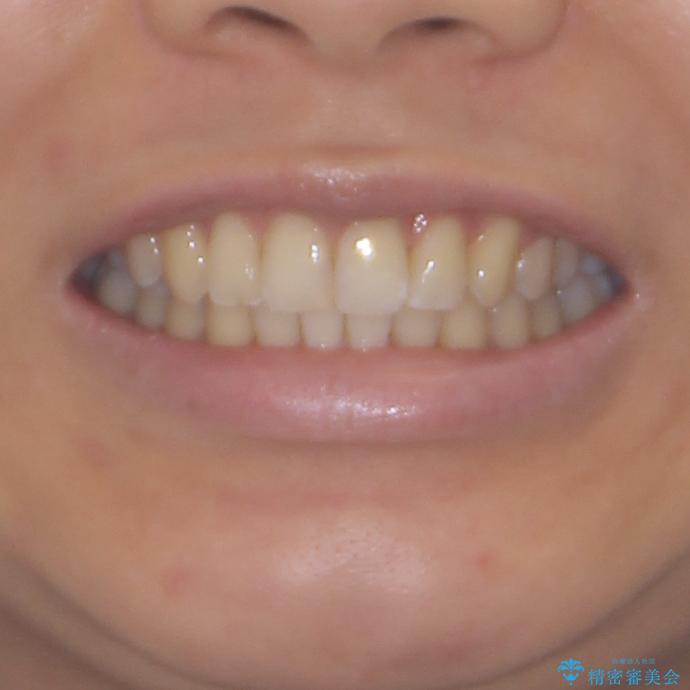

- 前歯の叢生と口元の閉じにくさを気にして来院された患者様です。

奥歯の咬み合わせを見ると、上顎が下顎に対して相対的に前方にありました。

口元の閉じにくさを改善するためには、上顎臼歯を後方に移動させた咬み合わせにする必要があります。

インビザライン単体で改善することも可能ですが、達成する可能性が高くないため、カリエールディスタライザーという補助装置を併用して、より確実性を上げることとしました。

奥歯の咬み合わせを改善しながら、並行してインビザラインで歯列を整えることとしました。

カリエールディスタライザーを併用したことで、確実かつ短期間で治療を終えることができました。